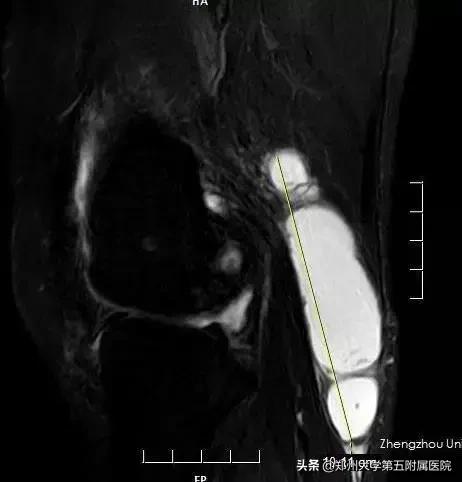

▲ 术前MRI检查巨大囊肿

▲ 术后复查MRI囊肿明显缩小,随着囊壁的闭合,囊肿会逐渐消失